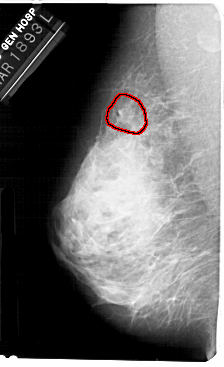

A_1361_1.LEFT_MLO

LEFT_MLO LINES 5491 PIXELS_PER_LINE 3346 BITS_PER_PIXEL 12 RESOLUTION 43.5 OVERLAY

FILE: A_1361_1.LEFT_MLO.OVERLAY

TOTAL_ABNORMALITIES 1

ABNORMALITY 1

LESION_TYPE MASS SHAPE IRREGULAR MARGINS OBSCURED

ASSESSMENT 3

SUBTLETY 1

PATHOLOGY BENIGN

TOTAL_OUTLINES 1

BOUNDARY